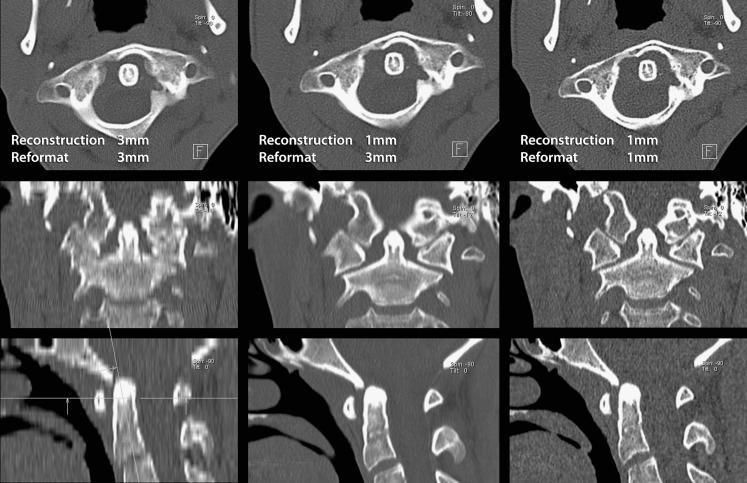

脊柱CT成像的技术层面

Technical aspects of CT imaging of the spine.

This review article discusses technical aspects of computed tomography (CT) imaging of the spine. Patient positioning, and its influence on image quality and movement artefact, is discussed. Particular emphasis is placed on the choice of scan parameters and their relation to image quality and radiation burden to the patient. Strategies to reduce radiation burden and artefact from metal implants are outlined. Data acquisition, processing, image display and steps to reduce artefact are reviewed. CT imaging of the spine is put into context with other imaging modalities for specific clinical indications or problems. This review aims to review underlying principles for image acquisition and to provide a rough guide for clinical problems without being prescriptive. Individual practice will always vary and reflect differences in local experience, technical provisions and clinical requirements.

这篇综述文章讨论了脊柱计算机断层扫描(CT)成像的技术方面。探讨了患者体位及其对图像质量和运动伪影的影响。特别强调了扫描参数的选择及其与图像质量和患者辐射负担的关系。概述了减少金属植入物辐射负担和伪影的策略。回顾了数据采集、处理、图像显示以及减少伪影的步骤。针对特定临床指征或问题,将脊柱CT成像与其他成像方式进行了对比。本综述旨在回顾图像采集的基本原则,并为临床问题提供一个大致的指导,而非给出具体的规定。个人实践总会有所不同,反映出当地经验、技术条件和临床需求的差异。